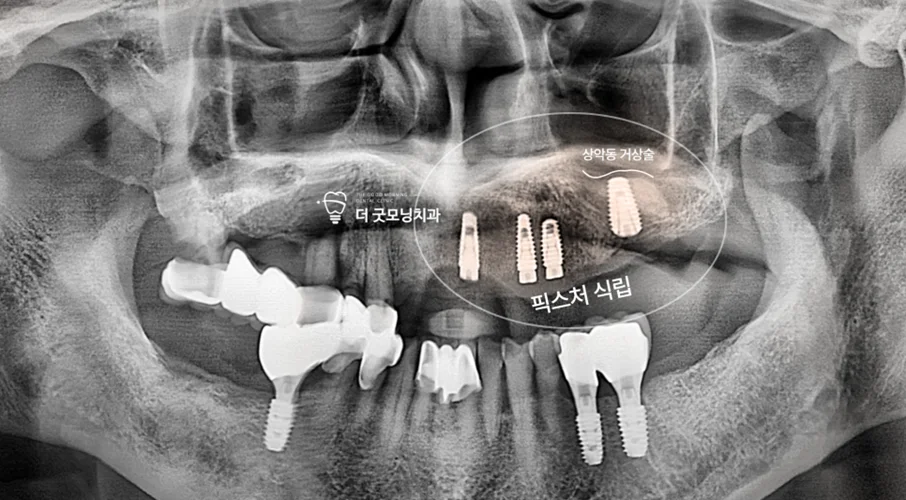

Step 4. 수면마취(의식하 진정) 하 좌측 수술

수술 전 맥박·호흡 등 생체징후 모니터링 장비를 세팅하고, 정맥 라인을 통해 약제를 천천히 투여하여 의식하 진정 상태에서 수술을 진행했습니다. 좌측 수술 시 상악동과의 거리가 가까워 상악동 거상술을 함께 시행하였으며, 4개 식립 중 3개를 사보험으로 처리했습니다.